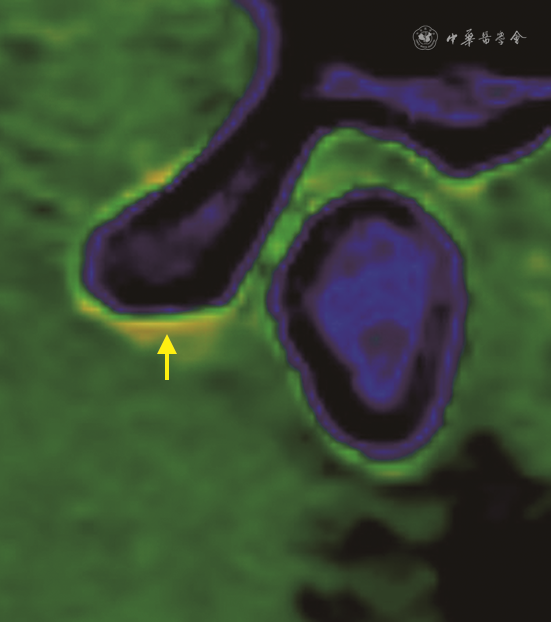

颞下颌关节腔分为上关节腔及下关节腔,关节上腔为1.0~1.2 ml,关节下腔为0.5~0.6 ml[5]。关节腔积液是TMJ滑膜炎的常见表现,常规影像学通常采用脂肪抑制T2加权成像评估,而传统CT对关节腔积液的评估欠佳。钙抑制CT成像技术通过对周围骨质的抑制可以显示关节腔积液,在既往研究中也证实钙抑制成像技术可以显示膝关节强积液[17]。同样颞下颌关节腔积液也可以在能谱CT钙抑制成像上得到显示(图6)。